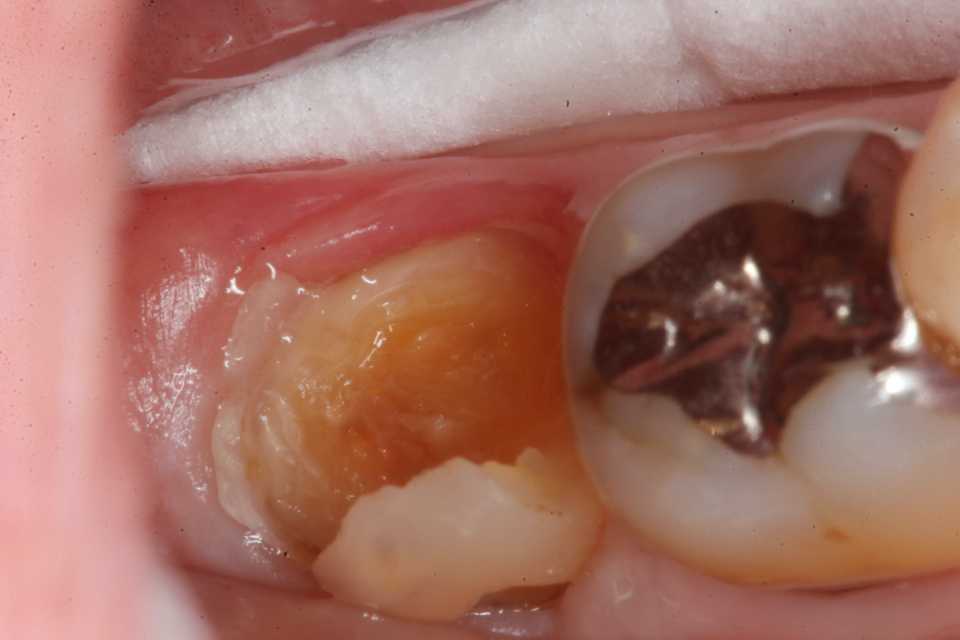

ストリップスを使わない隣接面CR(ダイレ… 2025.11.26

ストリップスを使わない隣接面CR(ダイレ… 2025.11.07